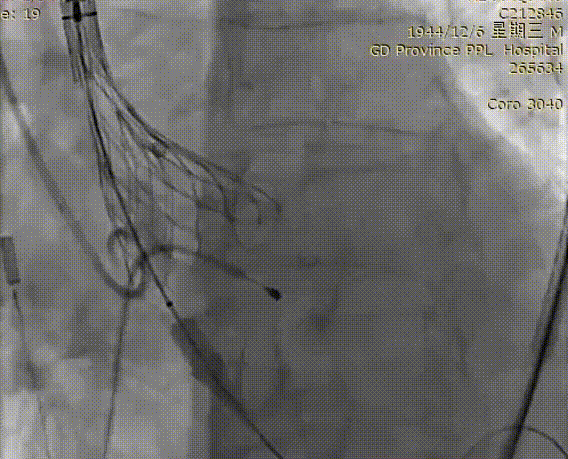

VitaFlow®第一次定位

释放2/3后造影确认位置

回收后再次定位

再次造影确定位置